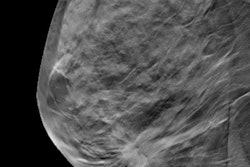

- PET, CT and radionuclide bone scans in the staging of early-stage breast cancer at low risk for metastasis

Vyas and colleagues looked at data dating from 2007 to 2015 from the Surveillance, Epidemiology, and End Results (SEER)-Medicare database, identifying 84,606 women ages 66 and older at the first primary diagnosis of stage 0 to stage II incident breast cancer during 2007 to 2015. They used the same database from the same time period to identify 55,705 men ages 66 and older at the first primary diagnosis of incident prostate cancer who had a Gleason score of 6 or less and a prostate-specific antigen (PSA) level of 10 ng/ml or less.

The proportion of patients who had at least one claim for PET, CT, or radionuclide bone scans in the three months prior to and three months following cancer diagnosis were identified for the period before publication of the ASCO Choosing Wisely recommendations in May 2012, and the postpublication period, after May 2012.